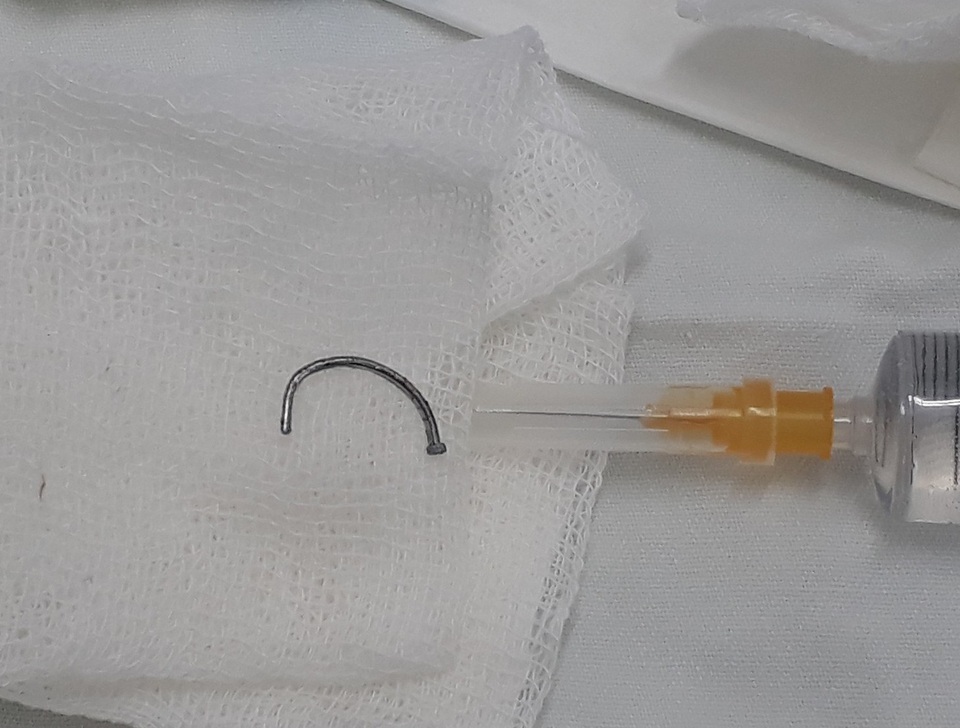

Trên hình ảnh phim X - quang các bác sĩ thấy một chiếc đinh cong, tiên lượng chưa xuyên thấu nhãn cầu nhưng dị vật này đã đâm xuyên giác mạc, qua mống mắc, xuyên qua thủy tinh thể làm đục vỡ thủy tinh thể. Kíp trực quyết định thực hiện ca phẫu thuật ngay trong đêm để rút dị vật đinh ra khỏi mắt bệnh nhân.

Qua tai nạn này, TS.BS Vân khuyến cáo người dân nên thực hiện đúng an toàn lao động để phòng tai nạn xảy ra. Trường hợp bệnh nhân T. là vô cùng may mắn, do chiếc đinh đã bị cong khi bắn ngược vào mắt, nhờ vậy mà chưa xuyên thấu, vỡ nhãn cầu. Nếu là đinh nhọn, với lực bắn mạnh như vậy, nguy cơ phải bỏ mắt là rất cao.